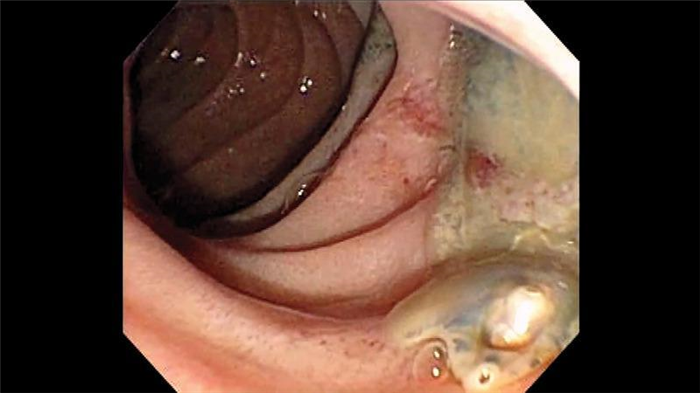

Состояние после вклинения камня и образования супрапапиллярного свища